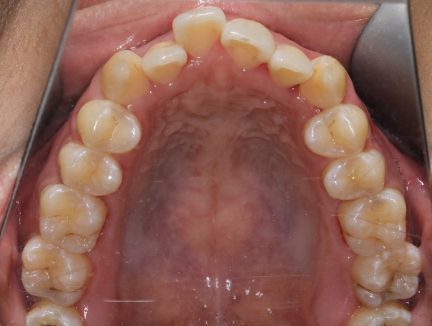

Case study 1

Before